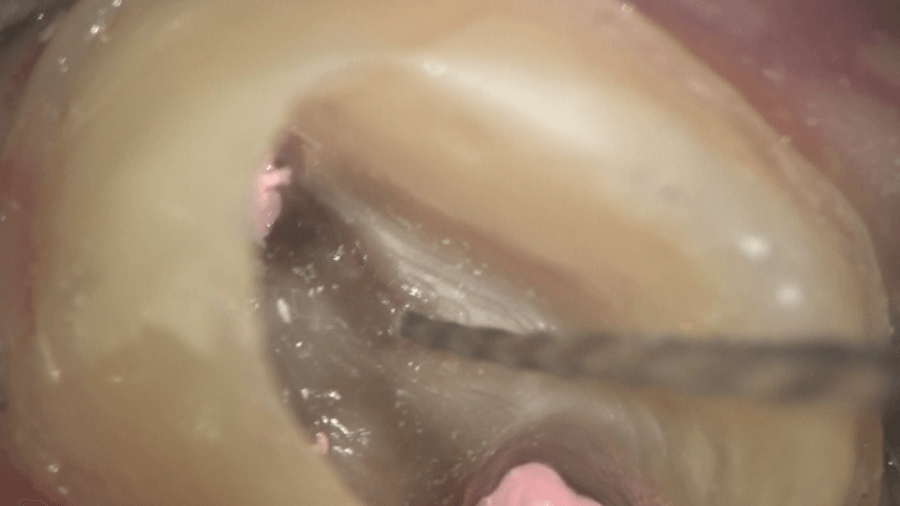

ラバーダムを施し、マイクロスコープで内部を確認すると・・・

黒丸で囲った部分に神経の一部が残っているように見えましたので、

ドリルを挿入すると、ドリルが入って行きました。

見落とされている根管がありました。いわゆる「MB2」と呼ばれる根管です。

そのすぐ隣にある根管から膿が出てきました。これは、痛そうですね。

きれいにした状況です。

その他の根管からは出血を認めました。

出血を止めて、よく確認すると、変な方向に穴ぼこが空いていました。出血はこの穴から出ていたのです。

どのタイミングかはわかりませんが、以前に治療した歯医者さんが空けてしまったのでしょう。